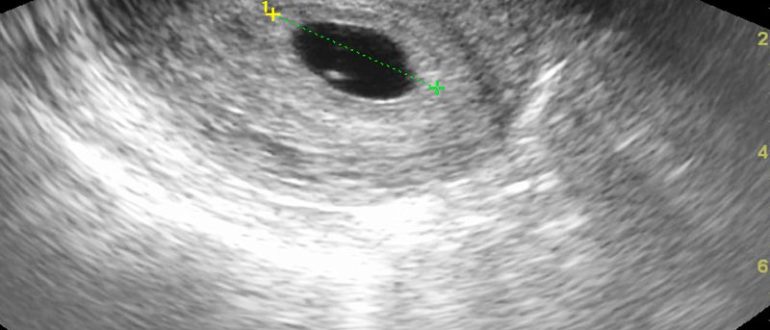

Внематочная беременность или маленький срок беременности?

Внематочная беременность: 4 первых признака и 7 главных причин, симптомы, как определить, лечение 04.02.201810.02.2018 Ольга Мигунова Внематочная беременность – аномальное состояние, которое несет серьезную угрозу жизни женщины. Место…